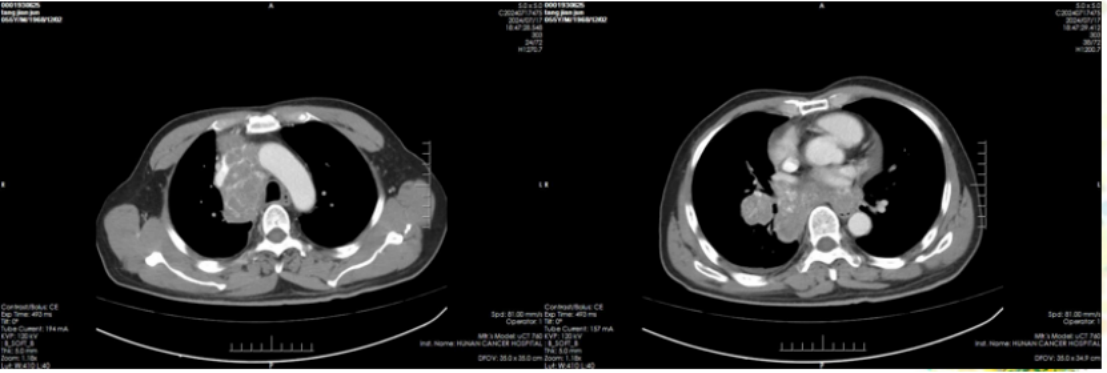

治疗前肺部(2024-5-14)提示:脑内多发结节肿块,考虑转移瘤可能性大(图1)。

图1

治疗后肺部(2024-7-17)提示:右下肺门区肿块较前缩小,阻塞性肺炎及肺不张较前缓解,右肺门、纵隔多发淋巴结转移瘤较前缩小,右侧胸腔积液较前减少(图2)。

图2